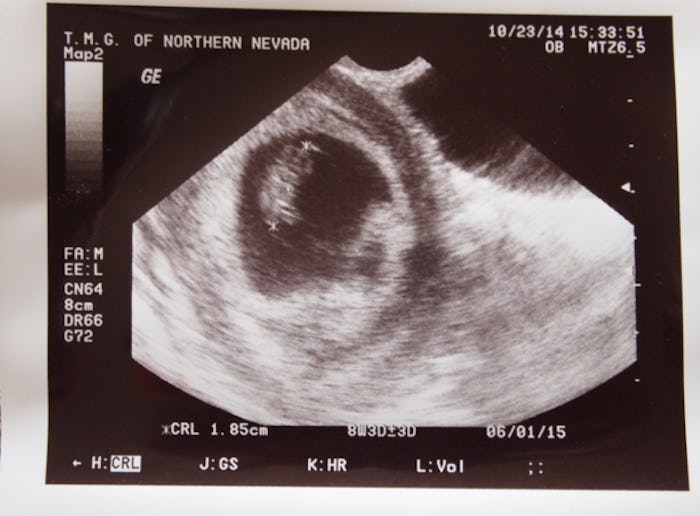

I stared at the screen with my midwife, willing movement, searching for a heartbeat, knowing it wasn’t going to happen. I could see it on her face the moment she turned on the ultrasound: I had suffered a miscarriage. My baby was dead. She pointed at the screen and asked if I saw what she saw, and I nodded and cried. It was just a floating dot, no tiny moving arms and legs, no beating heart. I should have been 12 weeks along, but it looked like the baby had stopped growing at nine.

I had a dream the night before the procedure that the doctor did another ultrasound and the heartbeat was still there, clear as day. It was comforting for a moment, then my senses came back to me.

I knew, I told him, but I needed the closure. The dream had left me unhinged. I knew what was coming, but there was a brief, unwelcome flutter of hope before the inevitable. He did the ultrasound. Still no heartbeat.